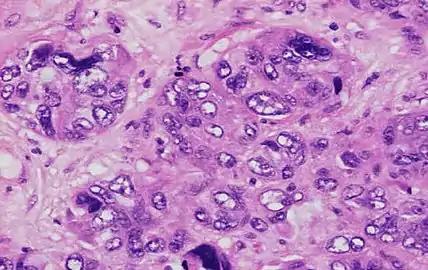

Invasive ductal carcinoma with marked nuclear pleomorphism.

- 3 points: nuclei with marked variation in size and shape